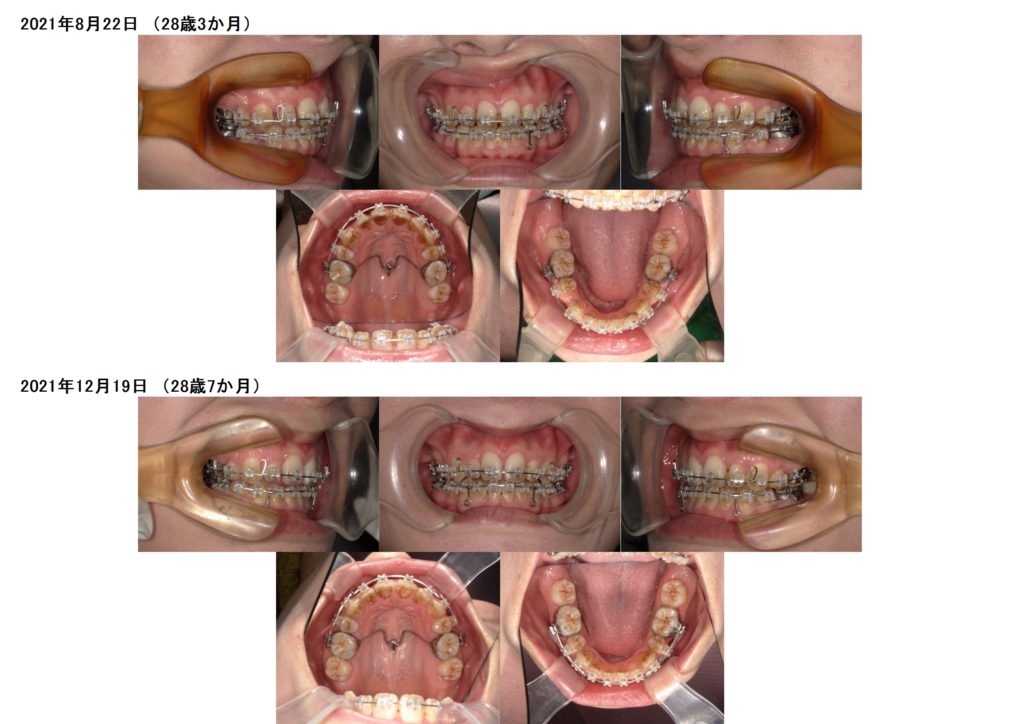

上顎にアンカースクリューを1本、パラタルバーが入っています。

初診時の検査から約4カ月。装置を着けてからそんなに期間は経過していませんがしっかりと歯が動いているのが分かります。

この患者様は奥歯を動かないように固定するためにアンカースクリューとパラタルバーを入れています。

徐々に抜歯した隙間、特に上顎の隙間がぐんぐんと閉じていっているのが分かりますよね